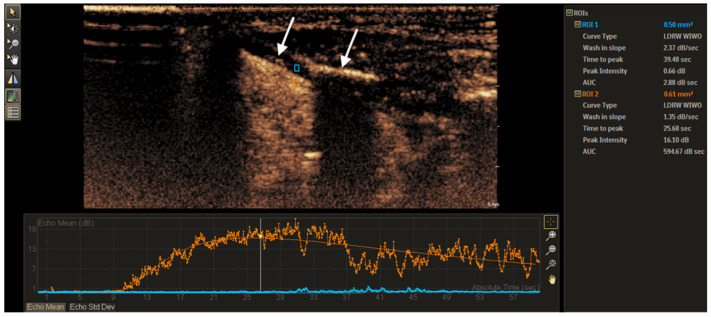

Objective: This study aimed to assess the diagnostic value of contrast-enhanced ultrasound (CEUS) time-intensity curve (TIC) parameters in detecting non-ossified thyroid cartilage invasion in patients with laryngeal squamous cell carcinoma (SCC). Methods: A CEUS TIC analysis was performed on 32 cases from 27 patients with histologically confirmed laryngeal SCC. The diagnostic performance of time to peak (TTP), peak intensity (PI), wash-in slope (WIS), area under the curve (AUC), and their quantitative differences (∆TTP, ∆PI, ∆WIS, and ∆AUC) to discriminate between the invaded and the non-invaded non-ossified thyroid cartilage was determined using ROC analysis. A logistic regression analysis was employed to identify significant predictors. Results: In an ROC analysis, of all TIC parameters analyzed separately, ∆TTP showed the greatest diagnostic performance (AUC: 0.85). A ∆TTP cut-off of ≤ 8.9 s differentiated between the invaded and the non-invaded non-ossified thyroid cartilage with a sensitivity of 100%, specificity of 76.9%, and accuracy of 81.3%. A combination of ∆TTP and PI increased the AUC to 0.93, specificity to 100%, and accuracy to 96.8%, but reduced the sensitivity to 83.3%. Meanwhile, the visual assessment of enhancement on CEUS to detect cartilage invasion had 83.3% sensitivity and 84.6% specificity. In a univariate logistic regression, only ∆TTP was a significant predictor of non-ossified thyroid cartilage invasion (OR: 0.80; 95% CI: 0.64-1.00). For every second increase in ∆TTP, the probability of thyroid cartilage invasion decreased by 20%. Conclusions: CEUS TIC parameters, particularly a combination of ∆TTP and PI, showed high diagnostic performance in the detection of non-ossified thyroid cartilage invasion in laryngeal SCC.

Abstract Image